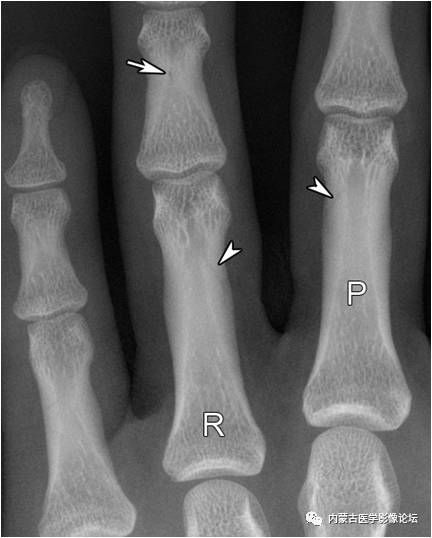

指骨滋养血管:箭头所示斜行透亮线影为近节指骨滋养血管,而白箭所示小圆形透亮区为中节指骨滋养血管轴位投照所致。注意指骨滋养血管从近端斜向远端,从骨皮质斜行走向髓腔,与掌骨相反。R:环指,P:近节指骨。

指骨Mach效应:箭头所示为环指(R)与小指骨结构内的软组织重叠影所形成的Mach效应,其走行与滋养血管影相反,也不应误为骨折线。